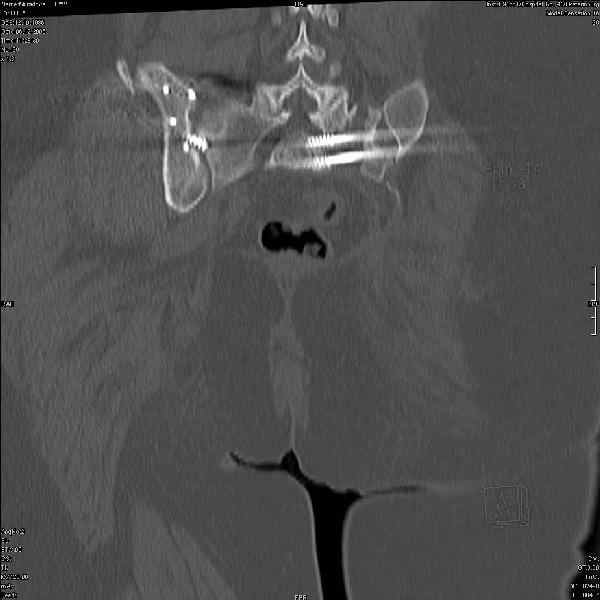

Здравствуйте, коллеги. Какие будут мнения по поводу лечения представляемой больной?

Молодая девушка 19 лет, травма 1 год назад, тогда же прооперирована.

В настоящее время имеются ноющие боли в области крестца слева, нарушение походки, ощущение неуверенности, слабости в левой нижней конечности, неврологически -непостоянные парестезии в левой нижней конечности. Ходит с дополнительной опорой, страдает от ожирения.

Какова по вашему будет оптимальная тактика в отношении несращения крестца? Замена винтов на более длинные с коррекцией их положения+ туннелизация зоны нестращения, открытое вмешательство с костной аутопластикой или еще какие варианты?

В приложении снимки при поступлении и послеоперационные год назад.

Могу сказать одно: миграция винтов и нестабильность синтеза левого подвздошно-крестцовогоо сочленения очевидна.